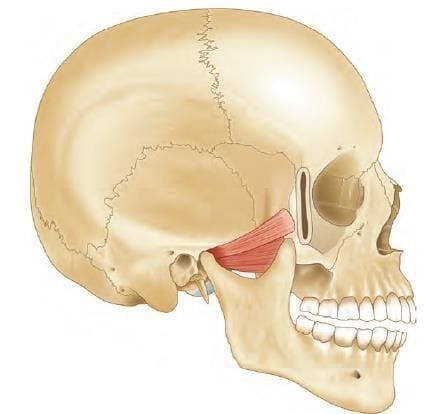

A fracture at the marked arrow (pterion) leads to bleeding of which artery? (AIIMS June 2020)

Detailed Solution for Test: Anatomy - 3 - Question 12

The highlighted area is the pterion, beneath which lies the anterior division of the middle meningeal artery, which may bleed if a fracture occurs at this location. The pterion marks the junction of four bones: the frontal, parietal, and temporal bones, along with the greater wing of the sphenoid bone. The central point of the pterion is referred to as the Sylvian point, where the cranium is notably thin.

• Its immediate deep relationships include the frontal (anterior) branch of the middle meningeal artery, its accompanying vein, and the stem of the lateral (Sylvian) sulcus of the cerebrum.

• The lateral sulcus extends posteroinferiorly from the Sylvian point, situated near the region of the pterion.

A fracture in this area can damage the middle meningeal artery, potentially leading to extradural haemorrhage. The pterion is crucial for the precise placement of burr holes for evacuating extradural haematomas. In neurosurgery, the pterional craniotomy is a frequently used technique to access the middle cranial fossa. Additionally, the pterion is the location of the anterolateral fontanelle, which closes at around six months after birth.